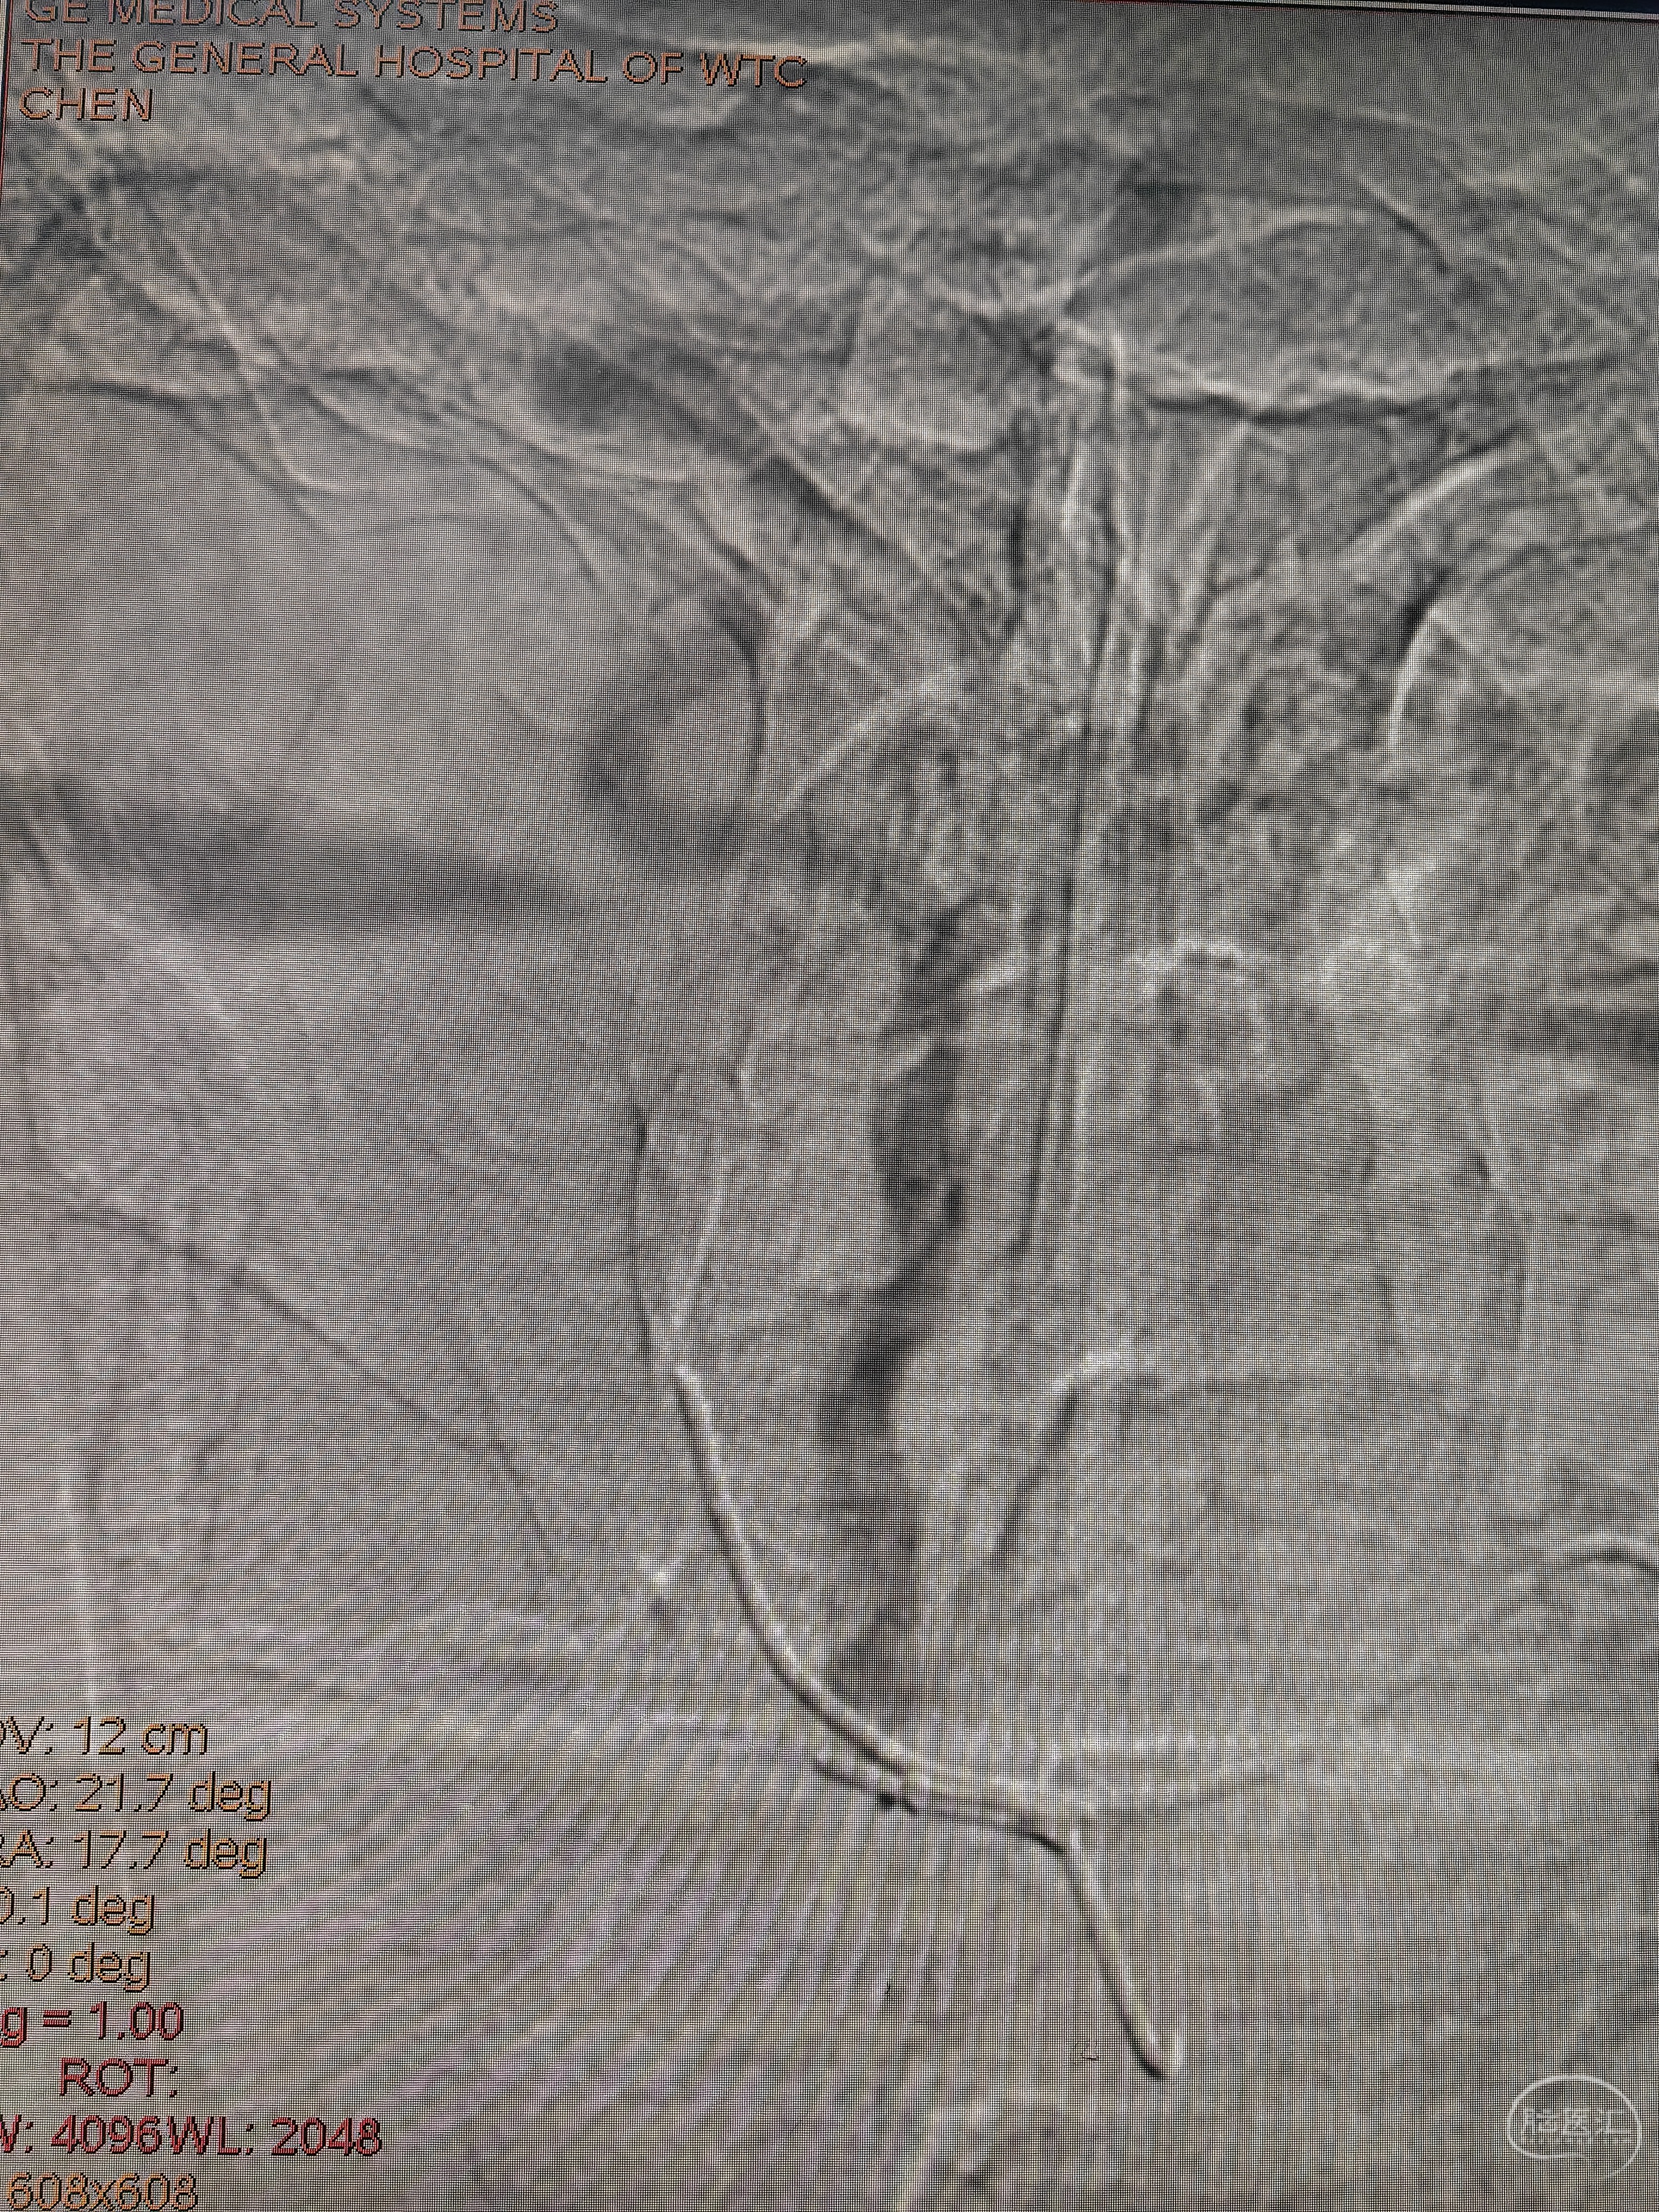

上SL-10微导管不行,加125管改变角度还是不行,此处省略长时间,最后的最后,想到用猪尾管切一半来提供角度便于支撑,but,猪尾长度110,guiding长度100,加个y阀无法出头,取了y阀裸上,不能路途不能造影,大概预估的角度上

这是猪尾切了的样子